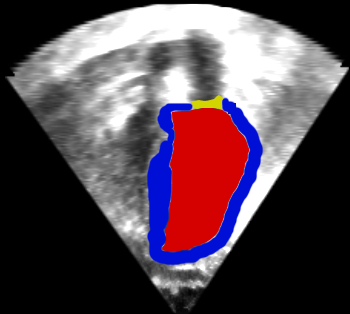

Fig. 9 shows an ultrasound image of the heart (left), an expert segmentation into blood pool, myocardium, and valves (middle) and the intensity distribution for the blood pool and outside the heart (right). These intensity distributions clearly overlap. We initialized the AMF model with this user-defined intensity distribution by sampling from the image followed by kernel-density estimation of the intensities. We re-estimated the intensity-distributions during the optimization. Specifically, given an intensity distribution, we compute the AMF solution, from that we obtain the binarized MAP solution that we use to re-estimate the intensity distributions using kernel-density estimation. We alternate AMF solution and density estimation to convergence. Fig. 9 shows the results of the AMF model for the estimation of label probabilities. The intensity ambiguity is captured in the estimated label probabilities of the AMF model. Regularization behaves as expected: low regularization results in noisy label probability maps. Moderate to high regularization allows capturing of the blood pool (for the MAP solution) while declaring other regions ambiguous or low-probability. Very large regularization declares the full image ambiguous, as expected, because the model will, in this case, prefer overly large segmentation regions.